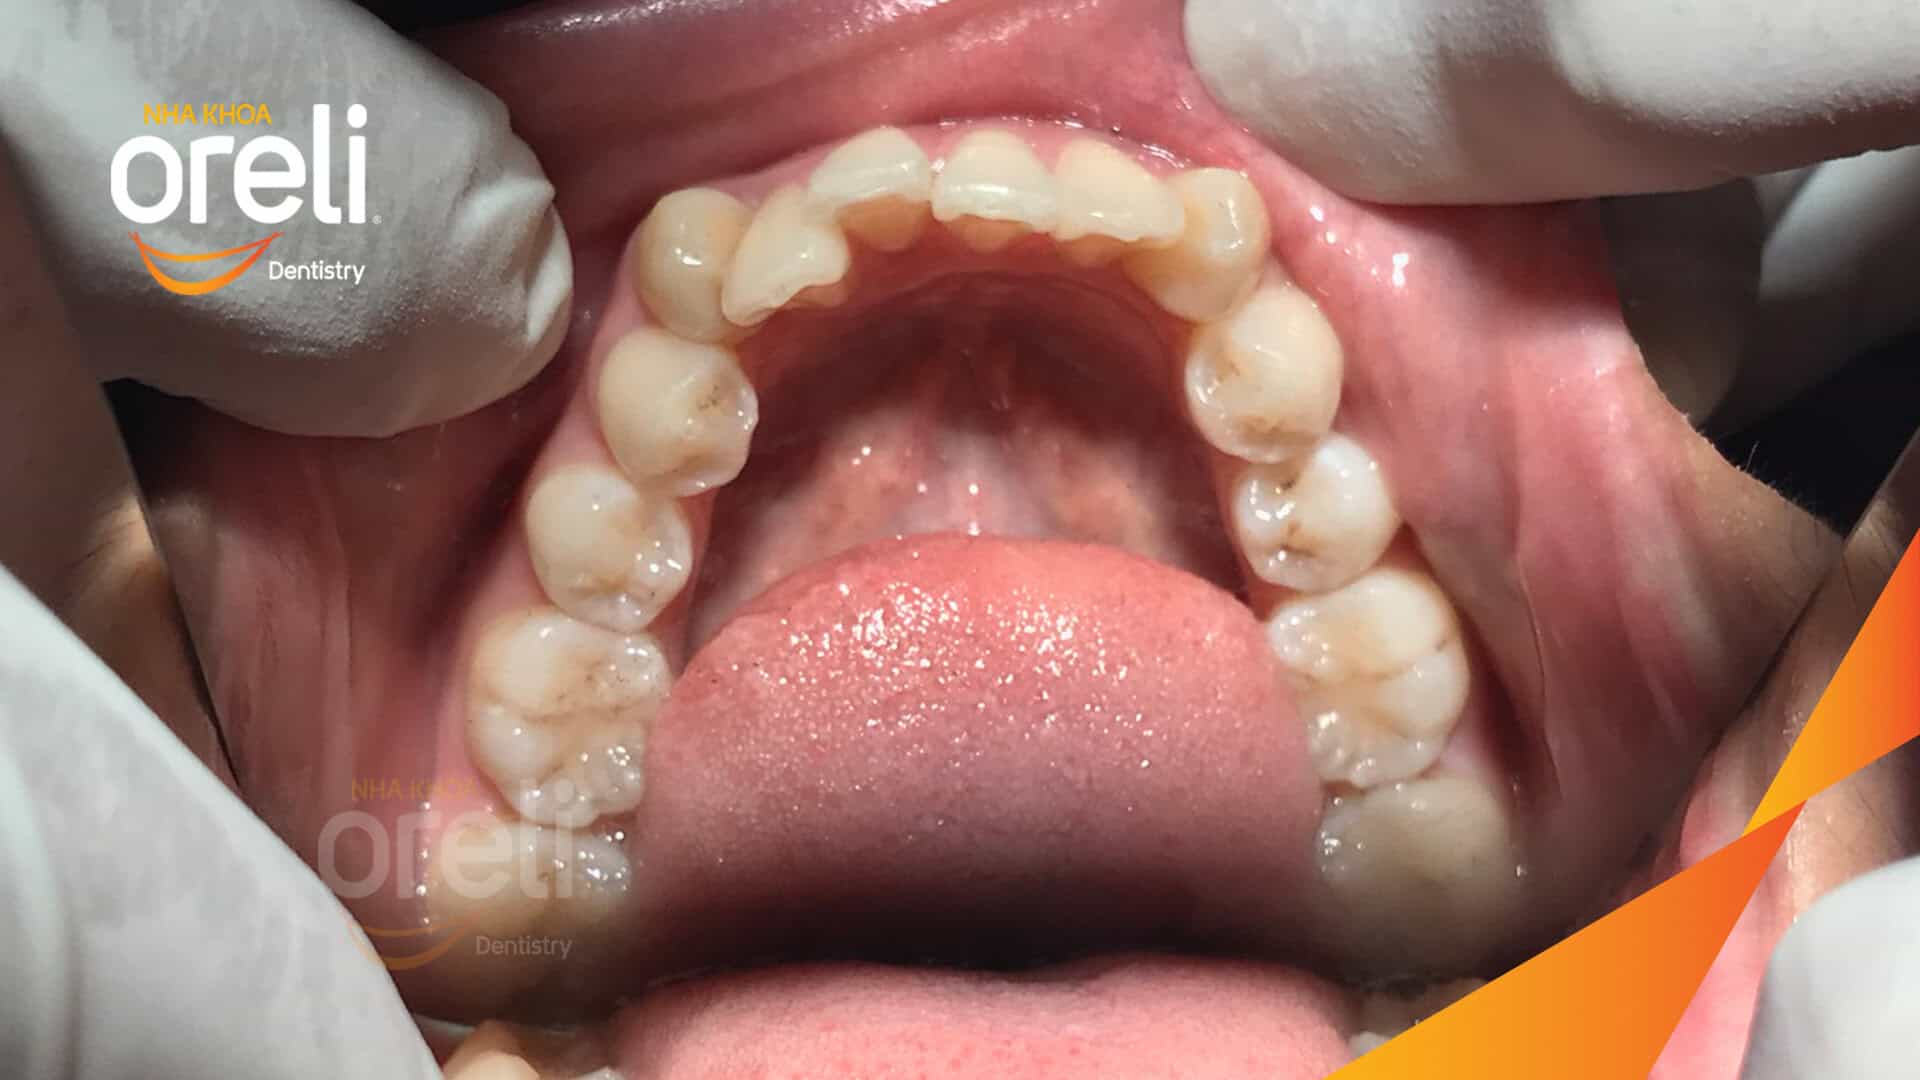

Tình trạng: Răng hô nhô xương ổ hai hàm

Giải pháp: Nhổ 4 răng số 4 niềng răng với măc cài kim loại

Răng số 4 là răng ít chức năng hơn so với các răng khác trên cung hàm, trên phương diện thẩm mỹ răng số 4 trùng với răng số 5 theo chiều trước sau. Do vậy việc nhổ răng 4 hoặc răng số 5 trong chỉnh nha để nắn chỉnh răng hô thường được lựa chọn.